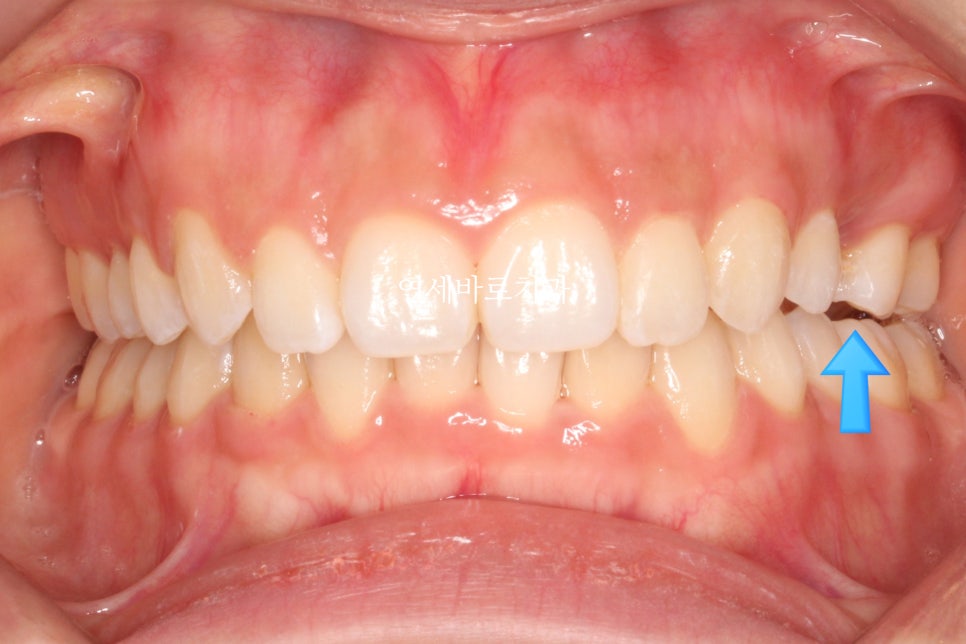

그리고 한개 치아의 #선천적결손 이 관찰됩니다.

화살표 부위가 결손치아입니다. 유치가 남아있네요.

임플란트를 안하기 위해 공간을 닫는 옵션과 임플란트를 하는 옵션 두개를 환자분과 상의하였습니다.

환자분은 비교적 치료기간이 짧은 #임플란트 식립 계획을 선택하셨습니다.

둘 다 맞는 치료계획입니다.